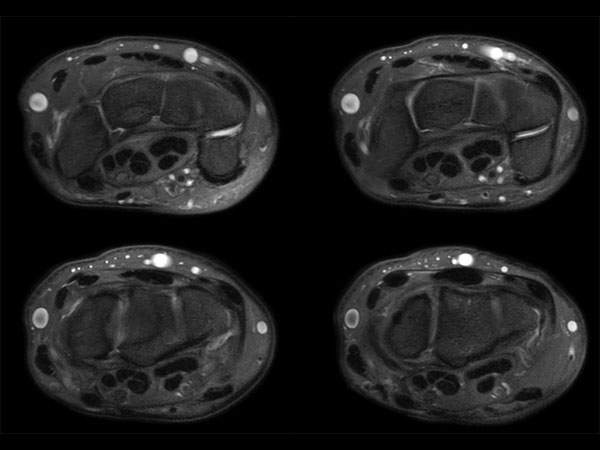

Wrist Imaging

Comprehensive Wrist imaging